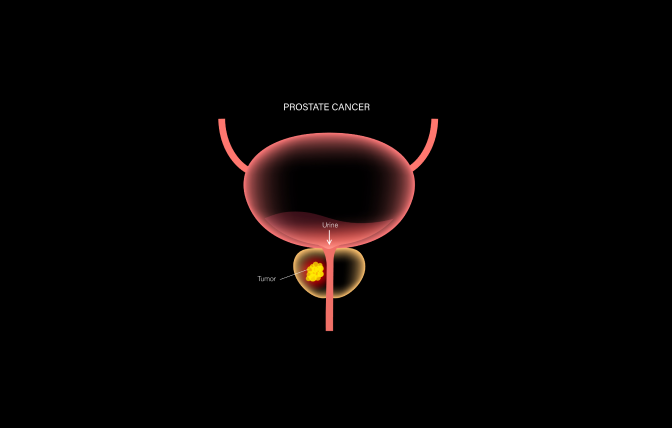

What is prostate cancer?

Prostate cancer is a common malignancy that forms in the prostate gland, located below the bladder in men. It develops when abnormal cells in the prostate grow uncontrollably, often without symptoms in the early stages.

How is prostate cancer diagnosed?

BeJoHo's expert diagnose prostate cancer through a digital rectal examination (DRE), a blood test called prostate-specific antigen (PSA) test, and a prostate biopsy.